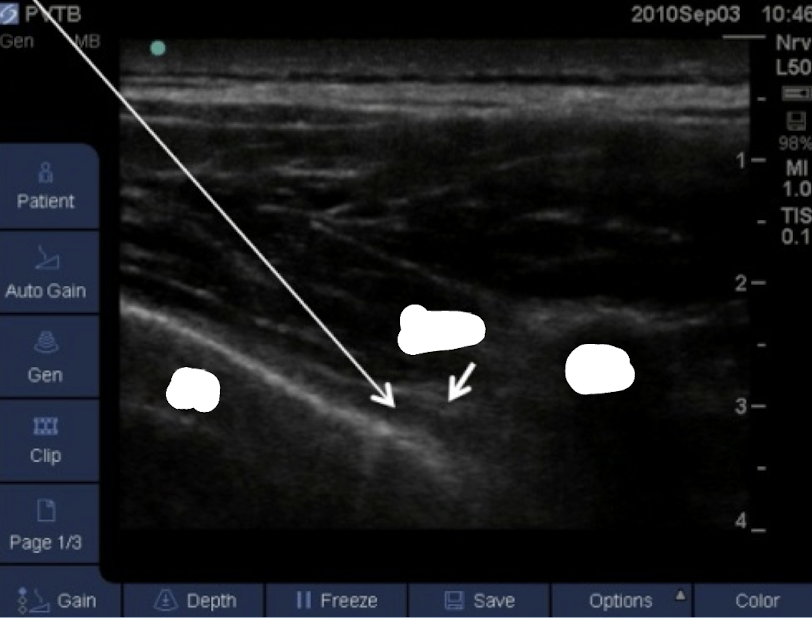

Q

name this block

A

transverse in plane PVB